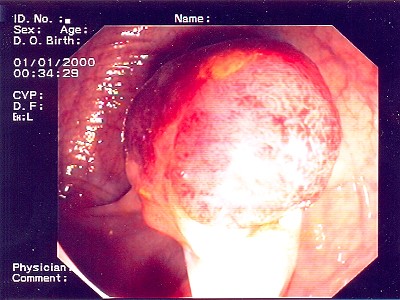

Großer Polyp des Dickdarmes